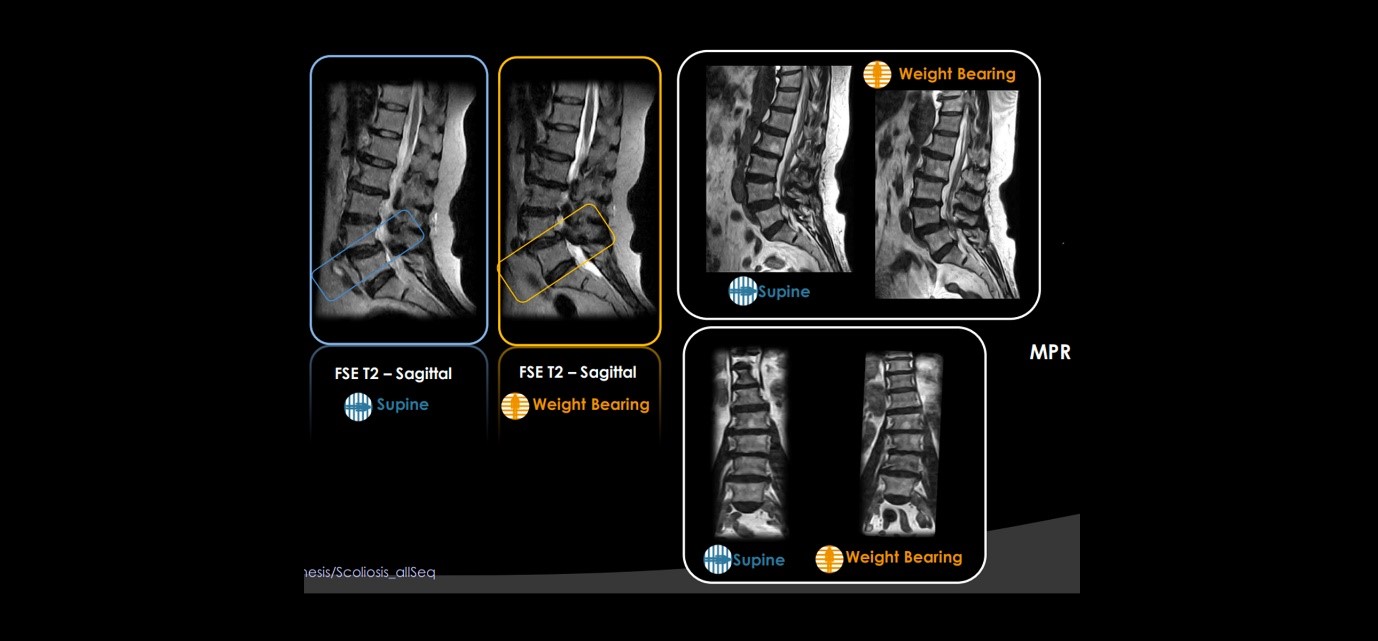

The G-scan Brio is a revolutionary MRI approach for all musculoskeletal applications, which allows you to increase your diagnostic accuracy and confidence. The open and tilting design is a new and innovative way of doing an MRI in which the position of the patient becomes an integral part of the outcome of the examination.

Open and tilting design is the new and innovative way of doing Weight-bearing MRI in which the position of the patient becomes an integral part of the outcome of the examination and allows patients to be imaged in horizontal and vertical positions and to perform Weight-bearing MRI examinations viewing anatomy in orthostatic positions of daily activities than traditional supine positions.

Traditional MRI exams are usually performed in supine positioning with the patient lying down on the scanner bed. However, this position does not reproduce the actual biomechanics of several joints and anatomies like knee, ankle, and spinal columns which are subjected to weight-bearing stress when we are walking or simply standing up.

In our center, Weight-bearing MRI is done to reproduce and study these joints in orthostatic position and find underlying pathologies that are difficult be assess with the conventional supine MRI.